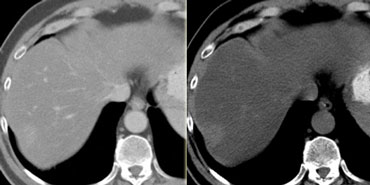

NECT, arterial and portal venous phase in a patient with Hepatitis C with two lesions in the liver (arrows). NECT, arterial and portal venous phase in a patient with Hepatitis C with two lesions in the liver (arrows).

In the arterial phase we see two hypervascular lesions.

Now do not just concentrate on the images, where you see the lesions best.

You have to look at all the other images, because they give you the clue to the diagnosis.

The upper images show a lesion that is isodens to the liver on the NECT.

In the arterial phase there is enhancement, but not as dense as the bloodpool.

In the portal venous phase the lesion is again isodense to the surrounding liver parenchyma and you can't see it.

If you only had the portal venous phase you surely would miss this lesion.

The lower images show a lesion that is visible on all images.

You see it on the NECT and you could say it is hypodens compared to the liver.

Does this help you?

No, not in the least.

However if you look at the bloodpool, you will notice that on all phases it is as dense as the bloodpool.

So we have a HCC in the right lobe on the upper images and a hemangioma in the left lobe on the lower images.

The key is to look at all the phases.